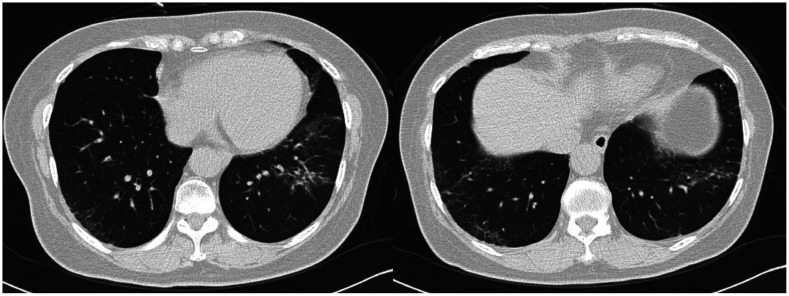

The anticancer drugs have evolved significantly, spanning molecular targeted therapeutics (MTTs), immune checkpoint inhibitors (ICIs), chimeric antigen receptor T-cell (CAR-T) therapy, and antibody-drug conjugates (ADCs). Complications associated with these drugs vary widely based on their mechanisms of action. MTTs that target angiogenesis can often lead to complications related to ischemia or endothelial damage across various organs, whereas non-anti-angiogenic MTTs present unique complications derived from their specific pharmacological actions. ICIs are predominantly associated with immune-related adverse events, such as pneumonitis, colitis, hepatitis, thyroid disorders, hypophysitis, and sarcoid-like reactions. CAR-T therapy causes unique and severe complications including cytokine release syndrome and immune effector cell-associated neurotoxicity syndrome. ADCs tend to cause complications associated with cytotoxic payloads. A comprehensive understanding of these drug-specific toxicities, particularly using medical imaging, is essential for providing optimal patient care. Based on this knowledge, radiologists can play a pivotal role in multidisciplinary teams. Therefore, radiologists must stay up-to-date on the imaging characteristics of these complications and the mechanisms underlying novel anticancer drugs.

Abstract Image